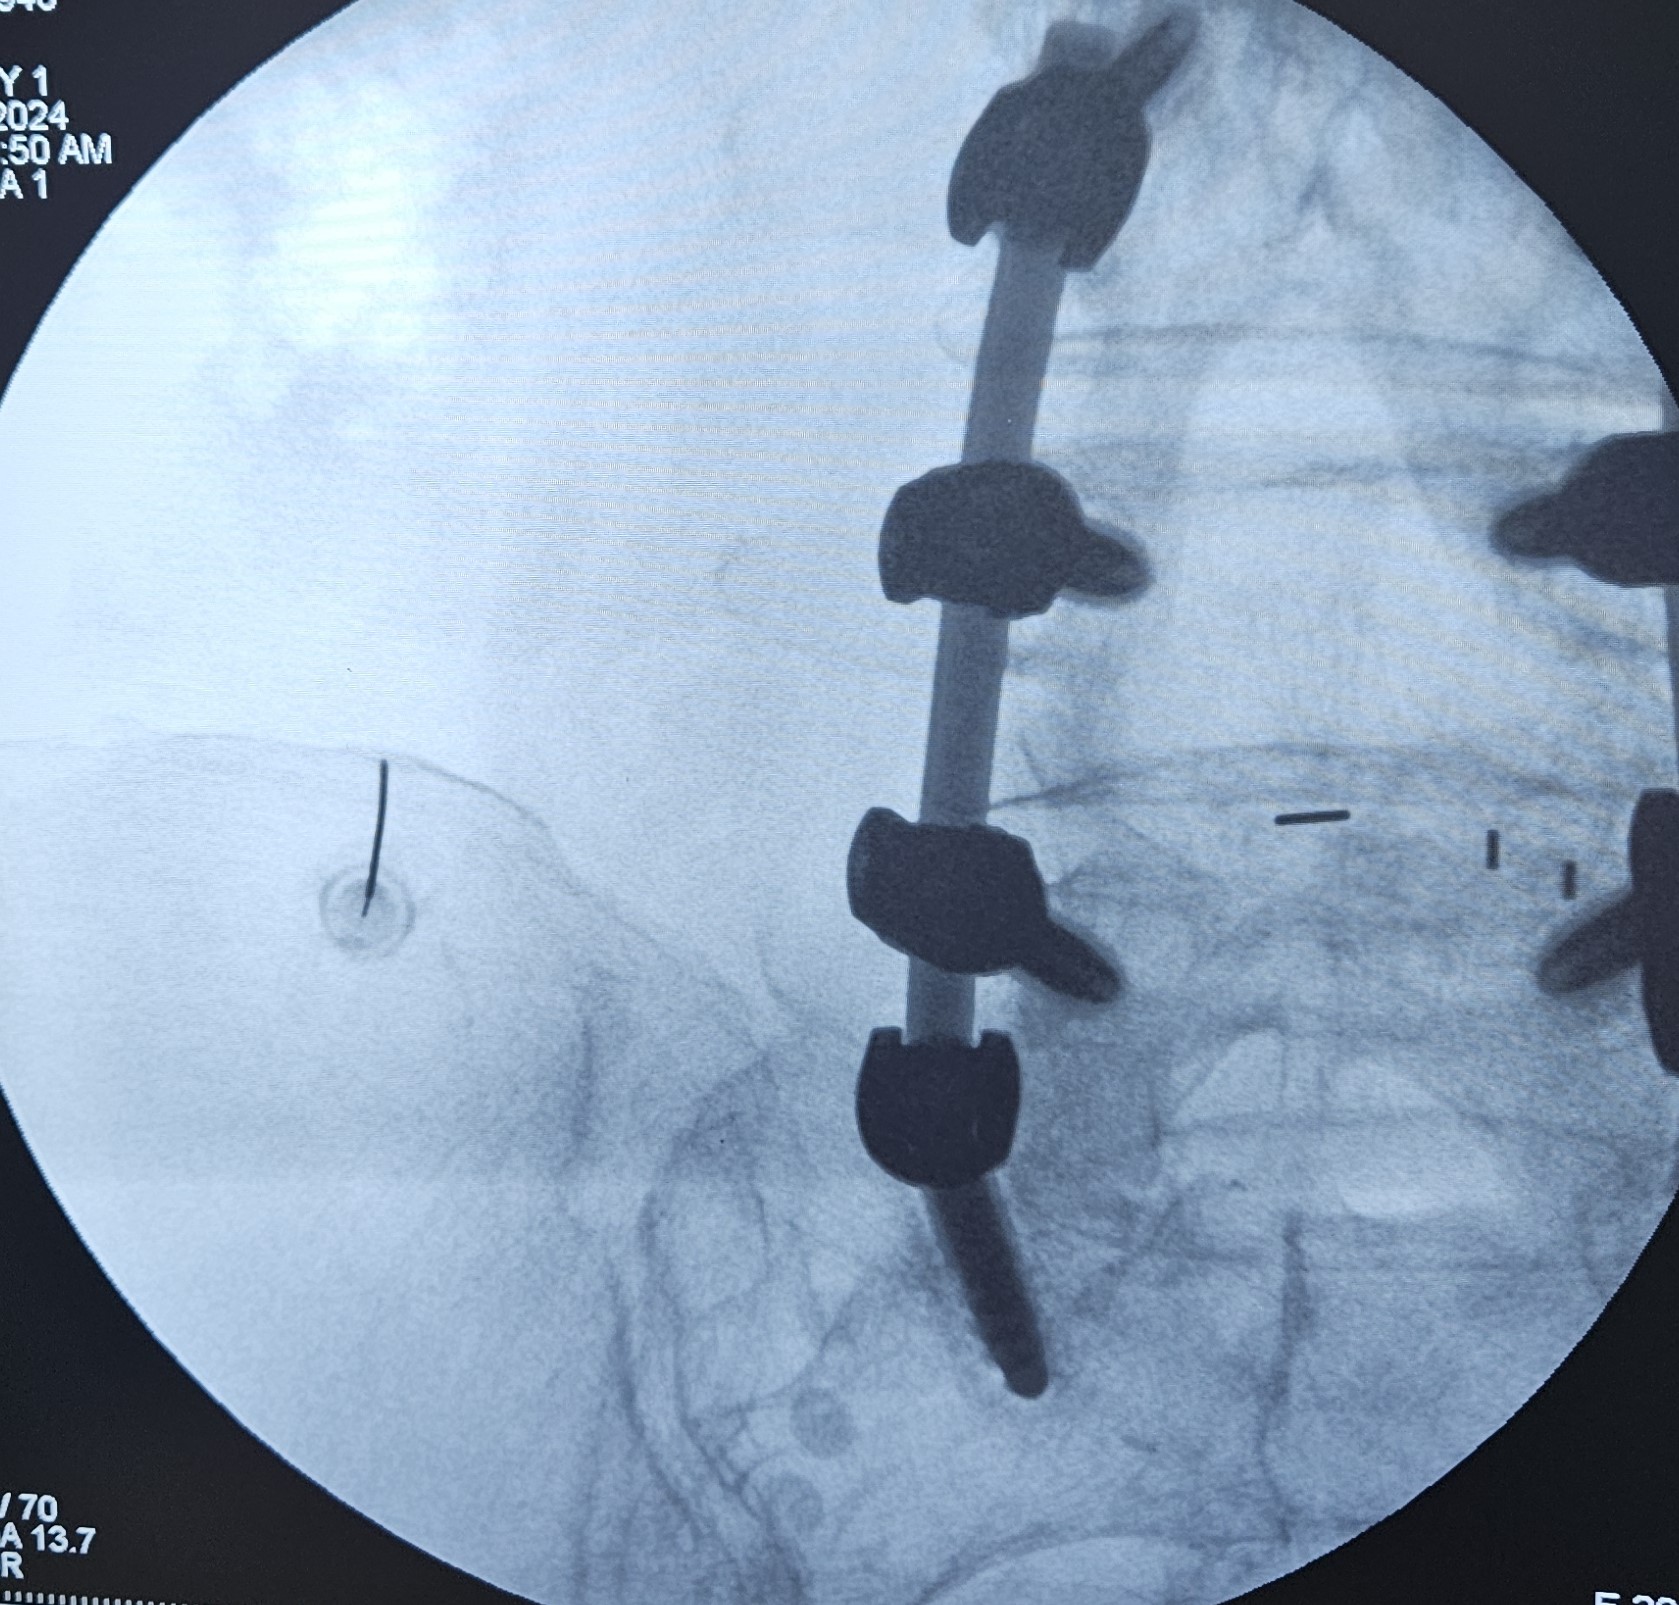

Πρόκειται για ελάχιστα επεμβατικές τεχνικές νευροτροποποίησης, δηλαδή αλλαγής του τρόπου αντίληψης του επώδυνου ερεθίσματος. Αυτό γίνεται με εμφύτευση ηλεκτροδίων επισκληριδίως (επισκληρίδια νευροδιέγερση) ή υποδορίως (περιφερική νευροδιέγερση) ανάλογα με την κατανομή του μετεγχειρητικού άλγους.